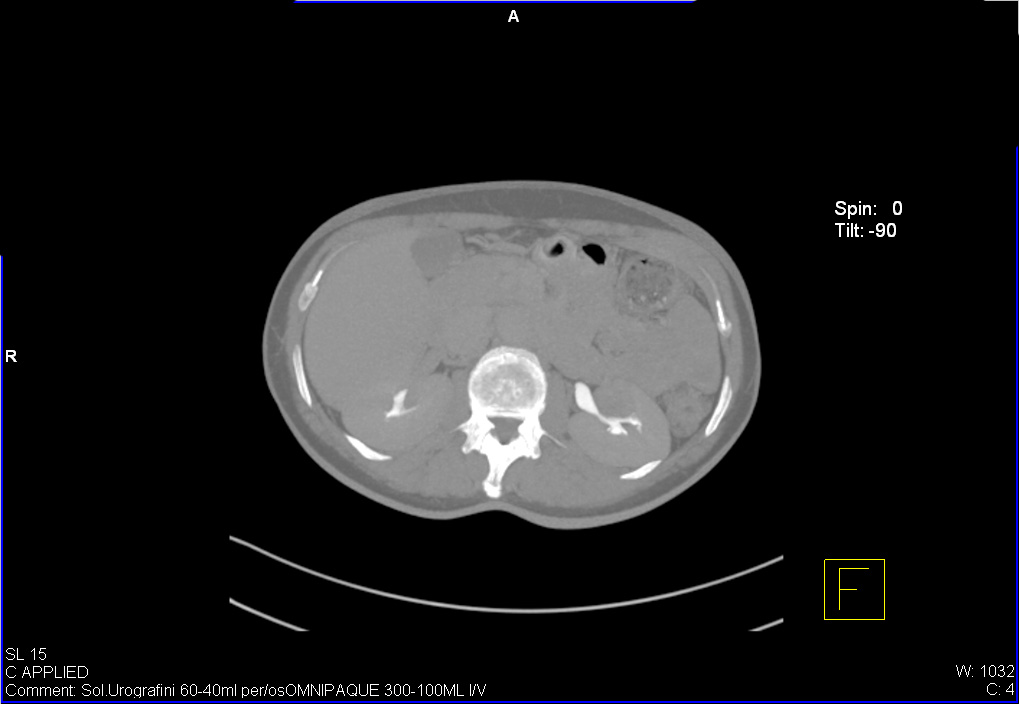

УЗИ почек - малый рак. Small RCC.

Женщина средних лет, жалоб нет.

Позвонили пациентке, она сделала КТ - новообразование подтверждено.

Гистологический диагноз - светлоклеточная аденокарцинома.